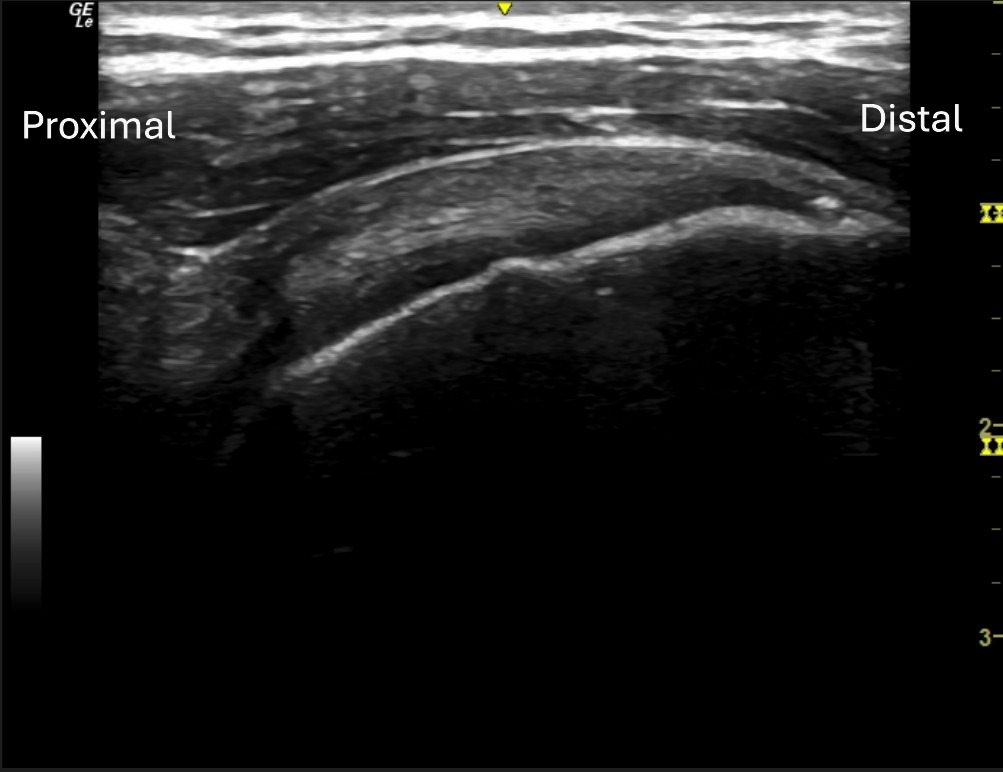

Unlabeled long axis view of the posterior supraspinatus at the articular surface.